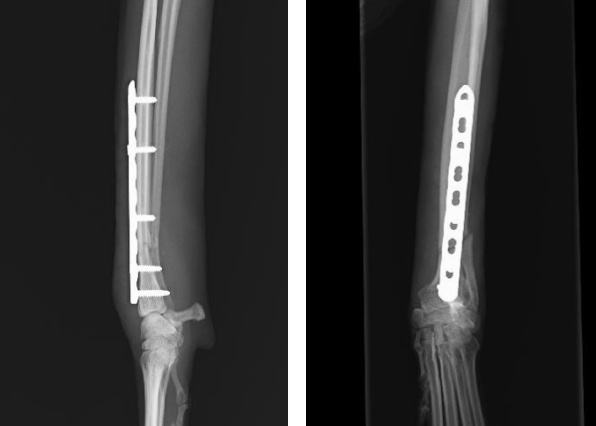

原因の多くは外傷(落下、踏み付け、交通事故)や骨腫瘍などがあります。特に近年多いのはトイ犬種のように足が細く長い犬種の落下事故による前足の骨折で、ソファや膝の高さの飛び降りでも起こります。激しい痛みで鳴く、手足を浮かせて歩く、じっとして動かないなどの症状が見られます。放置すると手足の変形や感染症などのリスクを伴います。治療には外科(金属のピン、プレート設置など)やギブス固定などがあります。

042-771-1112原因の多くは外傷(落下、踏み付け、交通事故)や骨腫瘍などがあります。特に近年多いのはトイ犬種のように足が細く長い犬種の落下事故による前足の骨折で、ソファや膝の高さの飛び降りでも起こります。激しい痛みで鳴く、手足を浮かせて歩く、じっとして動かないなどの症状が見られます。放置すると手足の変形や感染症などのリスクを伴います。治療には外科(金属のピン、プレート設置など)やギブス固定などがあります。